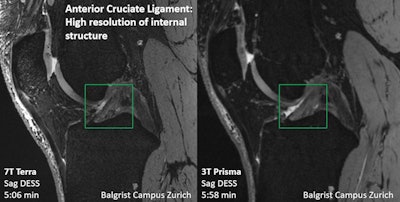

Direct comparison of the ACL with 7T and 3T. Image courtesy of Dr. Reto Sutter."[Studies have shown] that 7T MRI has higher diagnostic accuracy when it comes to visualizing low-grade meniscus and cartilage damage, and that [the technology] can be superior to 3T MRI for detecting small calcifications in articular cartilage and menisci," he said.